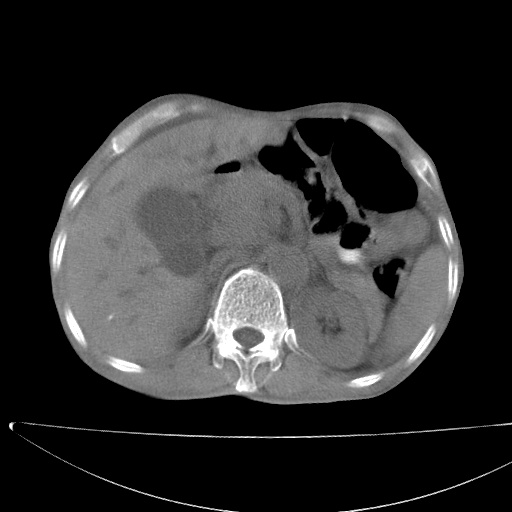

标题: CT17147:男70岁,上腹部不适1月。 [打印本页]

患者男70岁,上腹部不适1月。8年前有胃癌手术史。余病史不祥。

1)胃癌术后,复发不排除。

2)肝脏转移瘤。

3)肝脏钙化灶。

4)胆囊增大。

5)腹膜后多发性淋巴结转移。

6)腹水。

7)右侧少量胸水。

建议:增强扫描。